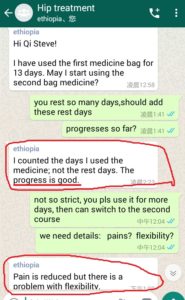

Following are some oversea patients recent feedback

Newly progresses(more will be uploaded soon)!

3. The gentleman in India just started May, 2019. Actually he started on April 28, 2019 but he used it in wrong way and got less effects, ONLY on May 8, 2019 during our follow-up, we found his wrong-doing, and then corrected him. ONLY in 2 days, his pains significantly reduced!!!!